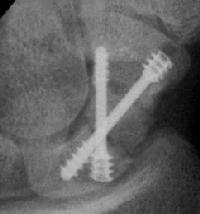

Case 7. This nonunion patient's scaphoid and iliac crest were unusually soft bone.

After two screws, the fixation was clearly inadequate, so I put a third screw through the graft into the proximal pole. I wasn't sure whether to buy

stock in Herbert screws or Zantac. The fracture healed despite AWOL and no immobilization.

Click for larger image